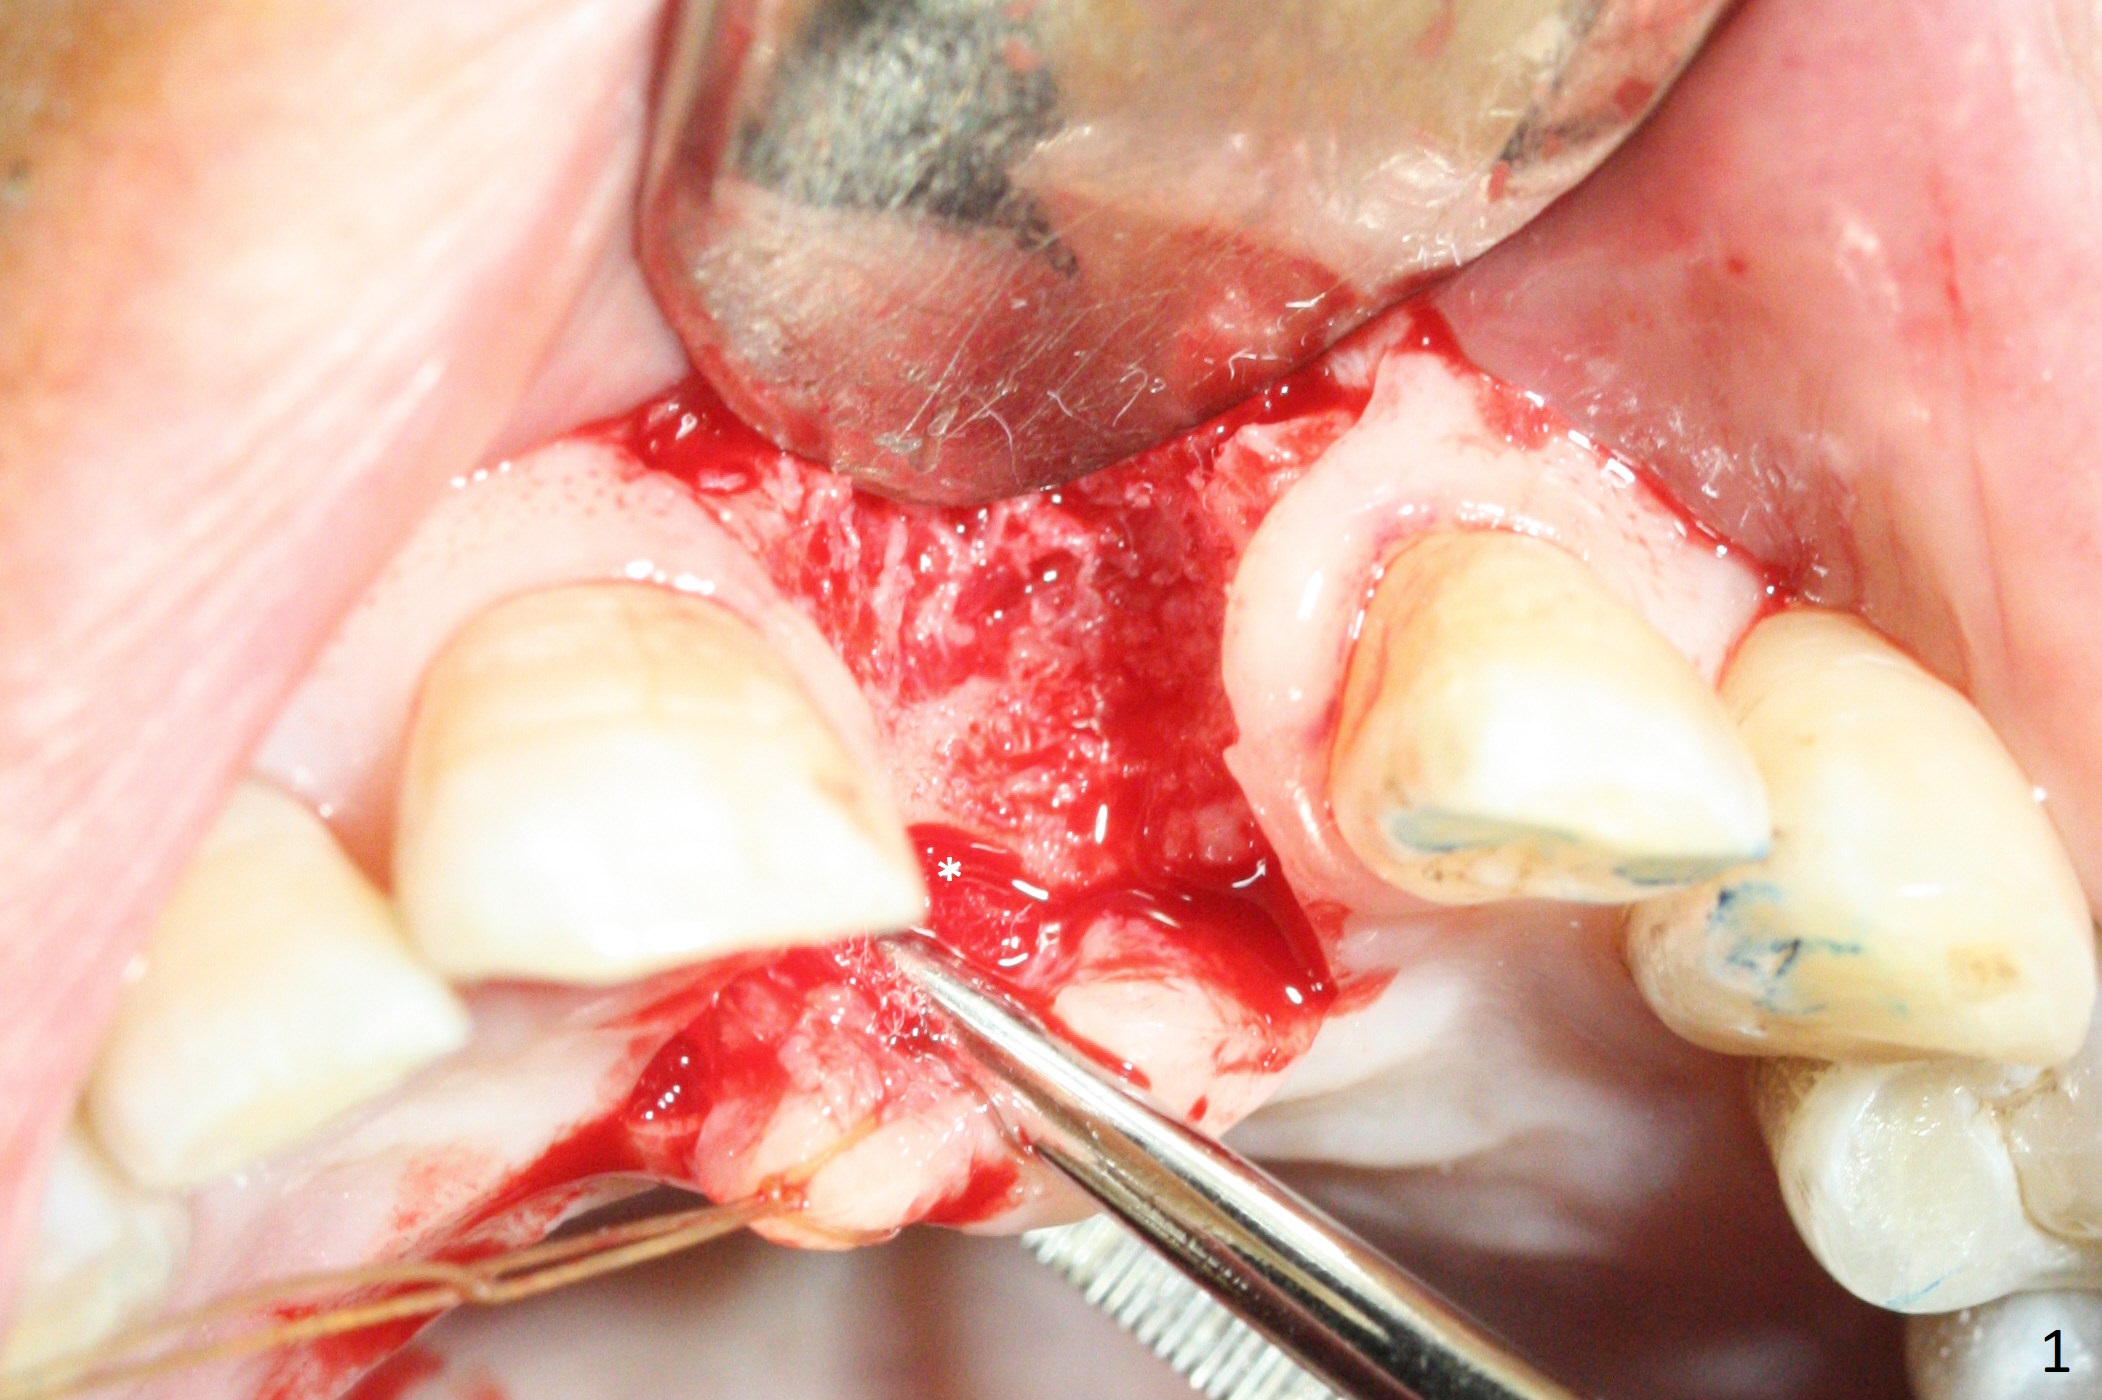

Preop examination shows mobility I of the teeth #8 and 10 and apparent occlusal trauma from #22-26 implant bridge. After occlusal equilibrium, incision reveals low, but moderate ridge at #9 (Fig.1). Fig.2a is a cross section of a normal upper incisor socket with thin buccal plate (B) and thick palatal one (P). It is difficult to initiate osteotomy in the oblique palatal wall when the buccal plate is resorbed (Fig.2b). In this case with horizontal buccal and palatal plate bone loss, the socket bottom is flat (Fig.2c), easy for osteotomy (Fig.2d green arrow, Fig.3). The initial osteotomy deviates mesial (Fig.3). To avoid perforation into the Incisive Canal, the trajectory is changed (Fig.4). After use of the final drill (3 mm), the coronal Incisive Canal is perforated. Following placement of a 3.5x13 mm implant and 4.5x5.5(4) mm abutment, Vanilla Graft is placed (Fig.5 *) to repair the perforation. Retrospectively, the coronal end of the Incisive Canal is revealed at incision (Fig.1 *). The initial osteotomy should be slightly more distal (Fig.3 black line). The buccal plate looks bulky due to placement of the abutment and bone graft 1 week postop (Fig.6,7 (crown dislodgement)). The bone graft appears to remain in place 2 months postop (Fig.8). Impression is taken because of instability of the immediate provisional (Fig.9 after Laser gingivectomy). The gingiva and buccal plate remain healthy 4.5 months postop (Fig.10). A permanent crown is cemented (Fig.11).